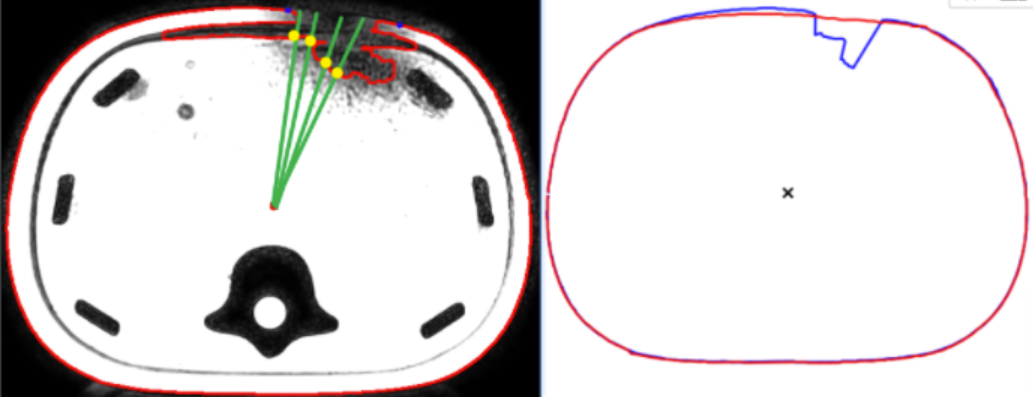

首先在图中使用极坐标系,质心为原点,如下图:

因轮廓是一周,即一个圆,在轮廓上采样180个点,即相邻点之间2°。

然后计算轮廓上点到质心半径,那么对于轮廓上每一个点都可以用(r,θ)来表示。

我们首先要对通过findcontours得到的轮廓进行采样,得到一周的点.即180个.

对原轮廓以这种方式进行轮廓采样:

比如上左图中轮廓采样后就是右图中蓝色轮廓。

如果凹陷部位完全缺失,相应角度上的点我们取质心作为轮廓点。

比如上图中在这个角度,轮廓上没有对应的点,此时设置轮廓点为质心。,取轮廓之后结果如下图。

对于下图中某一个角度上有内外两层轮廓,正常的是外层轮廓,所以我们取半径最大的点作为轮廓点.因此,对于外凸的缺口,我们就不能处理,在那种缺口中,某一个角度对应多层轮廓,应该取半径较小的.

注意:对于一个数据集,质心我取中间影像的质心(默认中间影像是“完好”的),所有影像公用这一个质心。

对当前轮廓(图中蓝色轮廓)和参考轮廓(图中红色轮廓)进行同步扫描。对于两个轮廓上相同θ的点的半径r,如果半径差大于设定的阈值,就认为是凹陷,如下图:

通过以上方式,我们能找到连续的凹陷点,两端就是凹陷的拐点,在两个拐点之间进行曲线拟合即可。